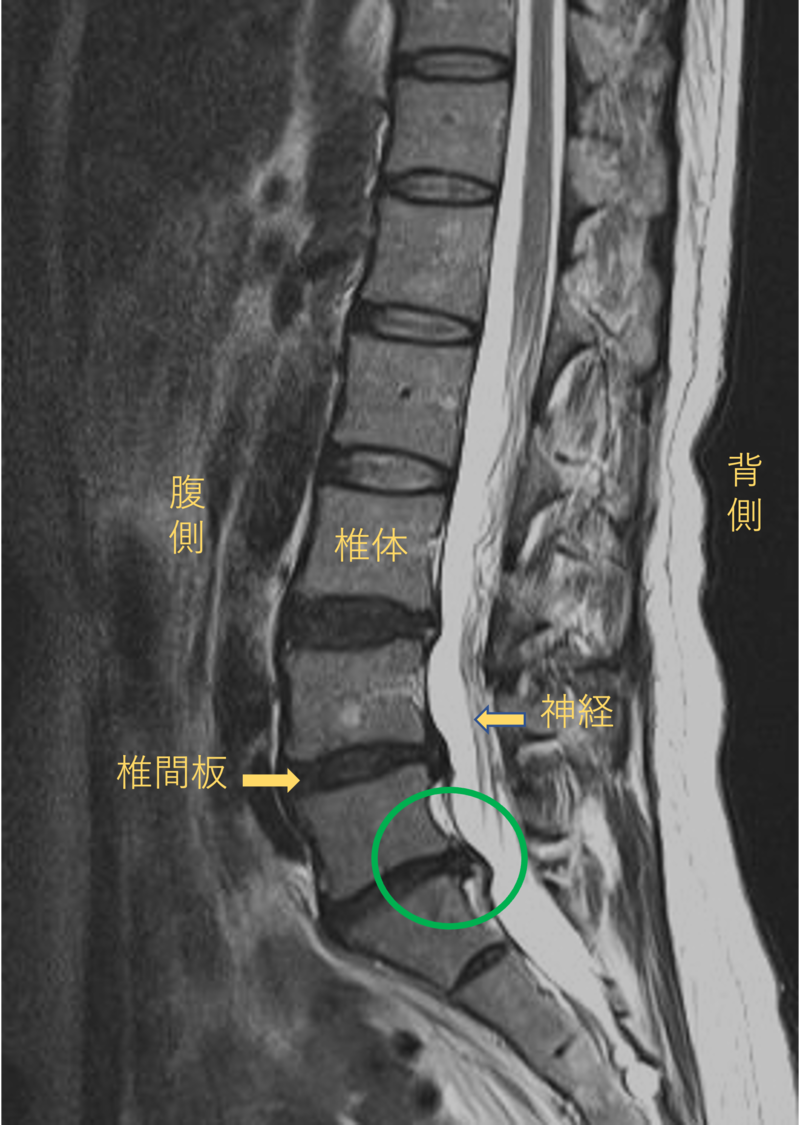

腰を横から見たMRI画像です。

腰椎という骨と骨の間に椎間板と呼ばれるクッションがあります。

このクッションの中身が飛び出す状態が椎間板ヘルニアと呼ばれます。

このMRI画像では、椎間板が背中側に飛び出して足に向かう神経が圧迫されることが痛みの原因となっておりました。